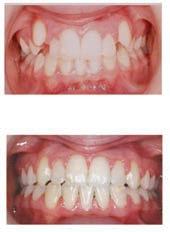

Christopher Chung, DMD

Smile Again Dental Group 818-776-9300

์์น์ง์ ๋ง์น๊ณ ๋์ ๊ฐ๊ธ ํ ๋ฒ ํ๋ฉด, ์

์์ด ํจ์ฌ ๊ฐ์ดํด์ง๊ณ ์์พํ ์ฃ . ์ฌ์ค ๊ฐ๊ธ์ ๊ทธ๋ฅ ์๋ฌด๊ฑฐ๋ ์จ๋ ๋ค ๋น์ทํ ๊ฒ ๊ฐ์ง๋ง, ์ฑ๋ถ๊ณผ ์ฉ๋

์ ๋ฐ๋ผ ๊ฝค ํฐ ์ฐจ์ด๊ฐ ์์ต๋๋ค. ์ด๋ค ๊ฐ๊ธ์ด ์น์ ๊ฑด๊ฐ์ ๋์์ด ๋๋ ์ง, ๋ ์ธ์ ์ด๋ป๊ฒ ์ฌ์ฉํ๋ ๊ฒ ์ข์์ง ์กฐ๊ธ ๋ ์์ธํ ์ ๋ฆฌํด๋ดค์ต๋ ๋ค.

๋จผ์ ๊ฐ์ฅ ํํ ๋ณผ ์ ์๋ ๊ฒ์ด ๋ถ์๊ฐ ๋ค์ด ์๋ ๊ฐ๊ธ์

๋๋ค. ๋ถ์๋

์ถฉ์น๋ฅผ ์๋ฐฉํ๋ ๋ฐ ์์ฃผ ์ค์ํ ์ฑ๋ถ์

๋๋ค.

์น์ ํ๋ฉด์ ๋ ๋จ๋จํ๊ฒ ๋ง๋ค์ด์ฃผ๊ณ , ์ฐ์ ์ํ ์์์ ์ค์ฌ์ฃผ์ฃ . ํนํ

์ถฉ์น๊ฐ ์์ฃผ ์๊ธฐ๊ฑฐ๋ ๋จ ์์์ ์์ฃผ ๋จน๋ ๋ถ๋ค, ์น์๊ฐ ์ฝํ๋ค๊ณ ๋๋ผ

๋ ๋ถ๋ค์๊ฒ ์ ์ฉํฉ๋๋ค. ๋ถ์ ๊ฐ๊ธ์ ํ๋ฃจ์ ํ ๋ฒ, ํนํ ์๊ธฐ ์ ์ฌ์ฉ

ํ๋ฉด ๋ ํจ๊ณผ์ ์ด์์. ๋ฐค์๋ ์นจ์ด ๋ ๋์์ ์ถฉ์น๊ฐ ๋ ์ฝ๊ฒ ์๊ธฐ๊ธฐ

๋๋ฌธ์, ์ ๋ ๋ถ์๊ฐ ์น์๋ฅผ ๋ณดํธํด์ฃผ๋ฉด ํจ์ฌ ๋ ๋ ํ์ฃ .

ํญ๊ท ์ฑ๋ถ

ํ ๊ฐ์ง ์ฃผ์ํ ์ ์ด ์์ด์. ๊ฐ๊ธ์ ๋๋ฌด ์์ฃผ ํ๋ ๊ฑด ์ข์ง ์์ต๋๋ค. ํ๋ฃจ์๋ ๋ช ๋ฒ์ฉ ์ต๊ด์ฒ๋ผ ๊ณ์ ์ฌ์ฉํ๋ฉด, ํด๋ก์ด ์ธ๊ท ๋ฟ ์๋๋ผ ์

์ ์ ํ์ํ ์ข์ ์ธ๊ท ๊น์ง ์ค์ด๋ค ์ ์์ต๋๋ค. ๊ทธ๋ฌ๋ฉด ์คํ๋ ค ๊ตฌ๊ฐ ํ๊ฒฝ

์ด ๋ถ์์ ํด์ง๊ณ , ์

์์ด ๊ฑด์กฐํด์ง ์ ์์ต๋๋ค. ๊ทธ๋์ ์ผ๋ฐ์ ์ผ๋ก๋

ํ๋ฃจ 1~2ํ ์ ๋๋ง ์ฌ์ฉํ๋ฉด ์ถฉ๋ถํฉ๋๋ค.

๊ฐ๊ธ์ ์น์์ ์๋ชธ ๊ฑด๊ฐ์ ์ง์ผ์ฃผ๋ ์ข์ ๋ณด์กฐ ์๋จ์ด์ง๋ง ์ด๋๊น์ง ๋ ๋ณด์กฐ์ผ ๋ฟ, ์นซ์์ง๊ณผ ์น์ค์ ๋์ ํ ์๋ ์์ต๋๋ค.

์์ ์๊ฒ ๋ง๋ ์ ํ์ ๊ณจ๋ผ์ ์ ์ ํ ๋์, ์ ๋นํ ํ์๋ก ์ฌ์ฉํ๋ ๊ฒ

์ด ๊ฐ์ฅ ํ๋ช

ํ ๋ฐฉ๋ฒ์

๊ทธ๋ค์์ ํญ๊ท ์ฑ๋ถ์ด ๋ค์ด ์๋ ๊ฐ๊ธ์

๋๋ค. ๋ํ์ ์ผ๋ก ํด๋ก๋ฅดํฅ์

๋ ์ฑ๋ถ์ด ์๋๋ฐ, ์ด๋ ์๋ชธ ์งํ์ด๋ ์ฌํ ์ผ์ฆ์ด ์์ ๋ ํจ๊ณผ์ ์

๋

๋ค. ์

์ ์ธ๊ท ์ ํ์คํ๊ฒ ์ต์ ํด์ฃผ์ง๋ง, ๋จ์ ๋ ์์ด์. ์ค๋ ์ฐ๋ฉด ์น

์๊ฐ ๋๋ ๊ฒ ์ฐฉ์๋๊ฑฐ๋ ์์ ๋ง์ด ๋ค๋ฅด๊ฒ ๋๊ปด์ง ์ ์์ต๋๋ค. ๊ทธ๋์

์ด๊ฑด ๋ณดํต ์น๊ณผ์์ ์ค์ผ์ผ๋ง์ด๋ ์๋ชธ ์น๋ฃ ํ์ ๋จ๊ธฐ๊ฐ ์ฒ๋ฐฉํ๋ ๊ฒฝ

์ฐ๊ฐ ๋ง์ต๋๋ค. ๋งค์ผ ์ฐ๋ ๋ฐ์ผ๋ฆฌ ๊ฐ๊ธ ์ด๋ผ๊ธฐ๋ณด๋ค๋ ์น๋ฃ์ฉ์ผ๋ก ์๊ฐ ํ์๋ฉด ๋ ๋ง์ต๋๋ค.